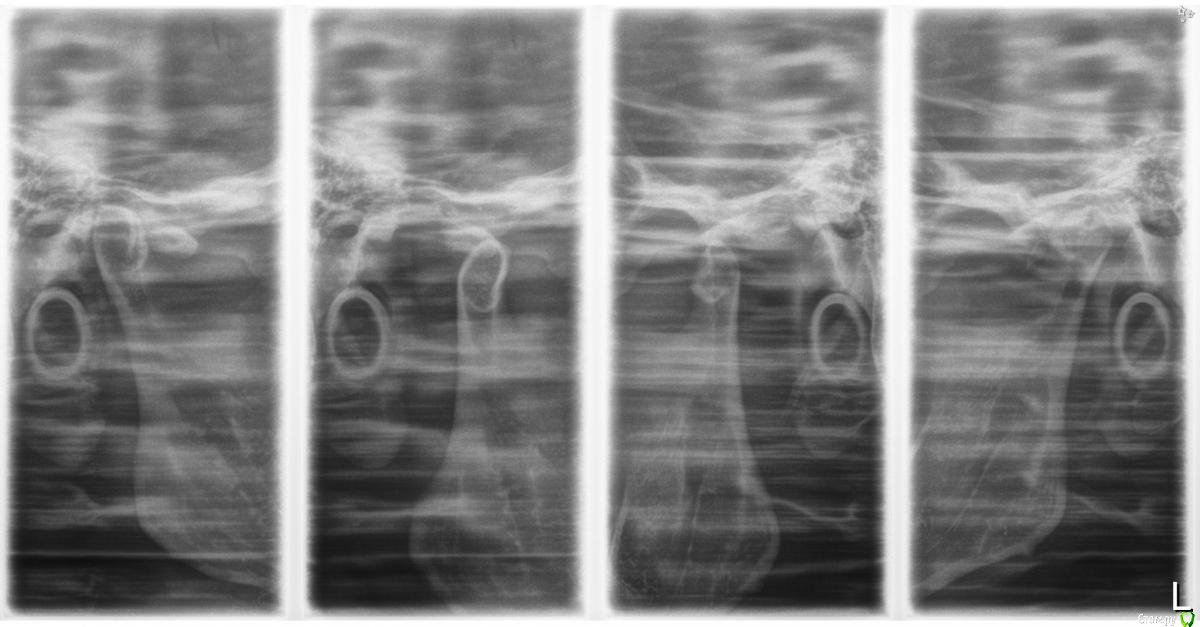

m.d.n Опубликовано 22 июня, 2016 Поделиться Опубликовано 22 июня, 2016 реконструкция оклюзионной плоскости нужна.выкладывайте фото .Так же кт суставов нужно , и гипсовка в артикулятор Ссылка на комментарий